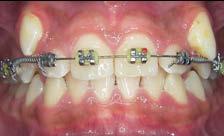

Los caninos retenidos constituyen una alteración eruptiva frecuente, con mayor prevalencia en la arcada superior. Su etiología es multifactorial y puede interferir con el trayecto normal de erupción, comprometiendo la oclusión y la estética.

Objetivo: Corregir una maloclusión Clase II división 2 mediante tratamiento ortodóntico en un paciente en crecimiento con ambos caninos superiores retenidos. Metodología: Se presenta el caso de un paciente masculino de 12 años, en dentición permanente, con perfil convexo, patrón dolicofacial y Clase II esquelética. Se realizó tratamiento ortodóntico sin extracciones. Para la tracción y alineación de los caninos retenidos se emplearon resortes abiertos (open coil springs) para la creación de espacio. Resultados: